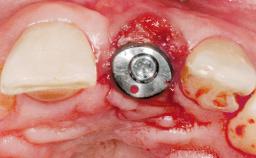

Early Placement of an Implant in a Maxillary Right Central Incisor Site

This 41-year-old female patient was referred to the clinic for the replacement of the right central incisor, since the tooth had developed a root fracture in the long axis that made extraction necessary. The healthy, non-smoking patient was first seen with the tooth still in place. A detailed Esthetic Risk Assessment was performed.The patient was worried about her dental esthetics and had high expectations for a successful treatment outcome from an esthetic point of view. The patient had a medium lip line that displayed parts of the gingiva in the anterior maxilla upon smile.

Bone Volume Deficient horizontally, allowing simultaneous augumentation

Esthetic Risk High